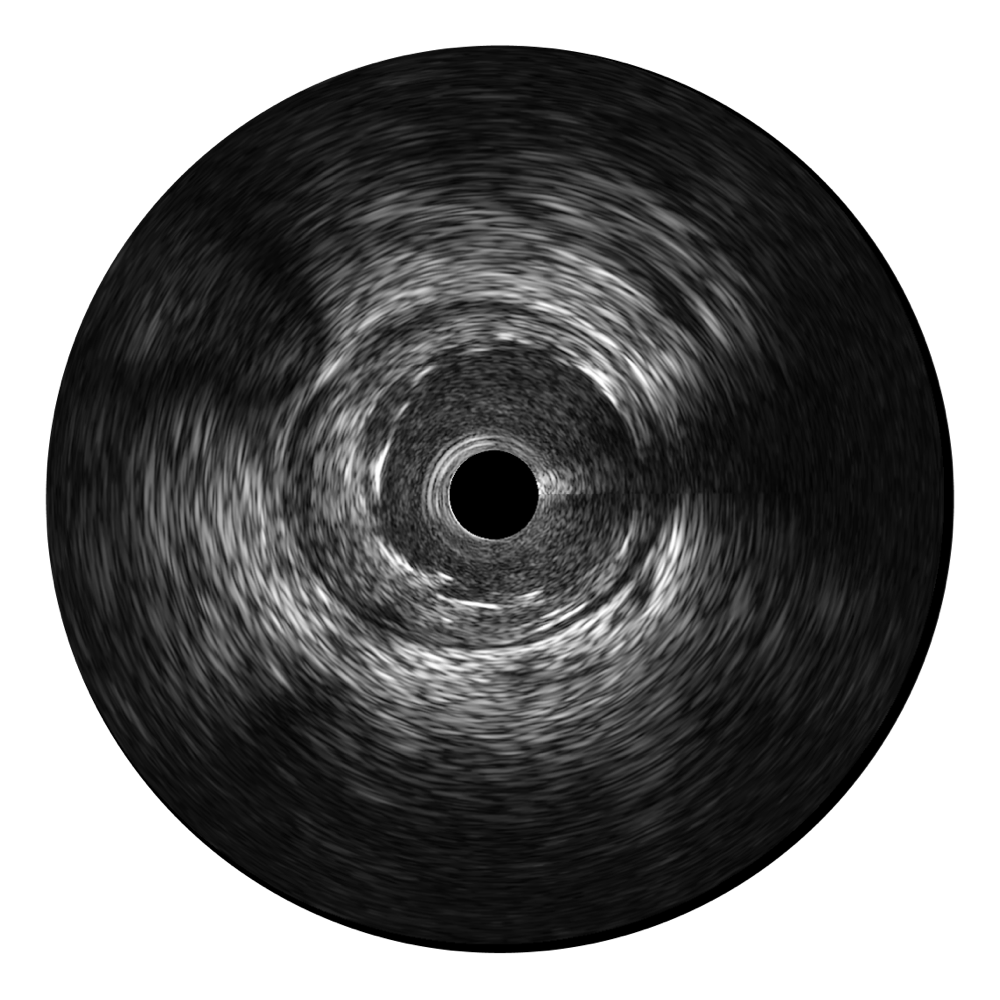

开立宽频IVUS图像

对比传统IVUS导管成像,开立宽频IVUS图像的近场支架梁显影更细腻,远场中膜外血管仍清晰可辨,兼顾远中近,兼顾分辨力与穿透深度